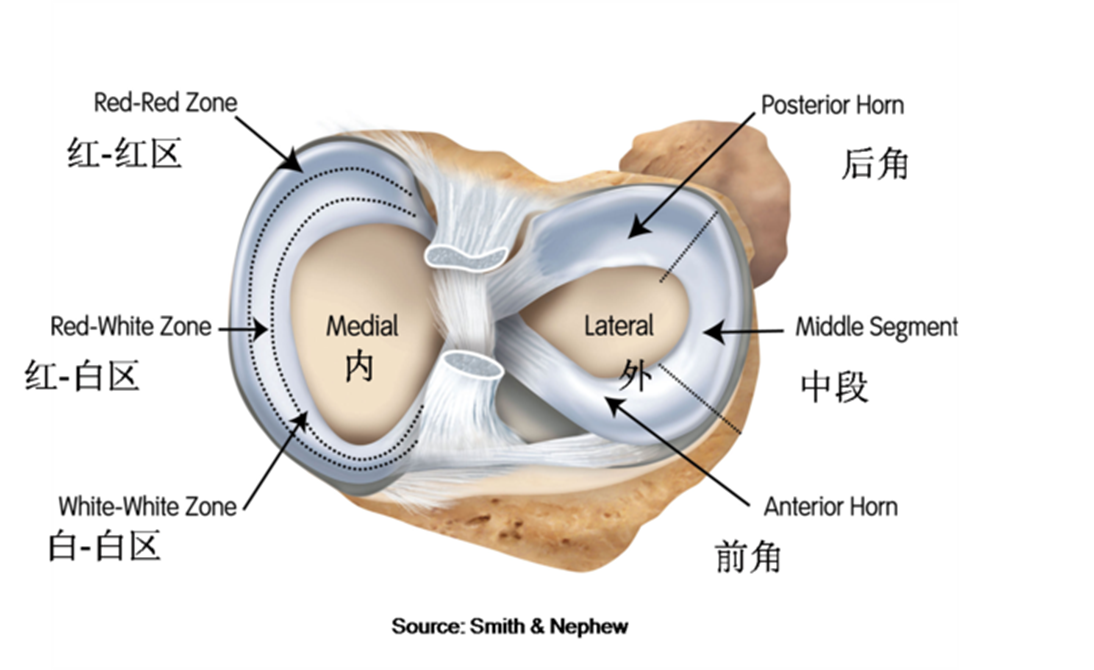

膝关节半月板的上面观

内侧半月板比较大,近似C形,有前后两角,前角狭窄后角宽大肥厚。前角附着于前交叉韧带附着点胫骨保间靖的前方。后角附着于后交叉韧带止点的前方,课间峰的后方,该处均无关节面。中部外缘与内侧副韧带的深层纤维相连,所以内侧半月板只有前半部稍松弛有活动的余地。

外侧半月板较小,形状似O形。前角附着于前交叉韧带止点的外侧方,踝间蟠的前方,而后角则附着在馔间醋的后方,后交叉韧带止点的前方。外缘与肌腿相连,不与外侧副韧带相连,所以外侧半月板的活动度比内侧半月板大。

红白区示意图

Muller 等将半月板分为三个区,即红-红区、红-白区及白-白区。红表示有血运,白表示无血运。红-红区撕裂位于滑膜缘有血运区,即撕裂之两侧缘均有充足血供,愈合能力很强。红-白区撕裂位于有血运和无血运的分界部,也有一定的愈合能力。而白-白区则完全无血运极难愈合。红-红区及红-白区撕裂在妥善的修复后均可愈合。